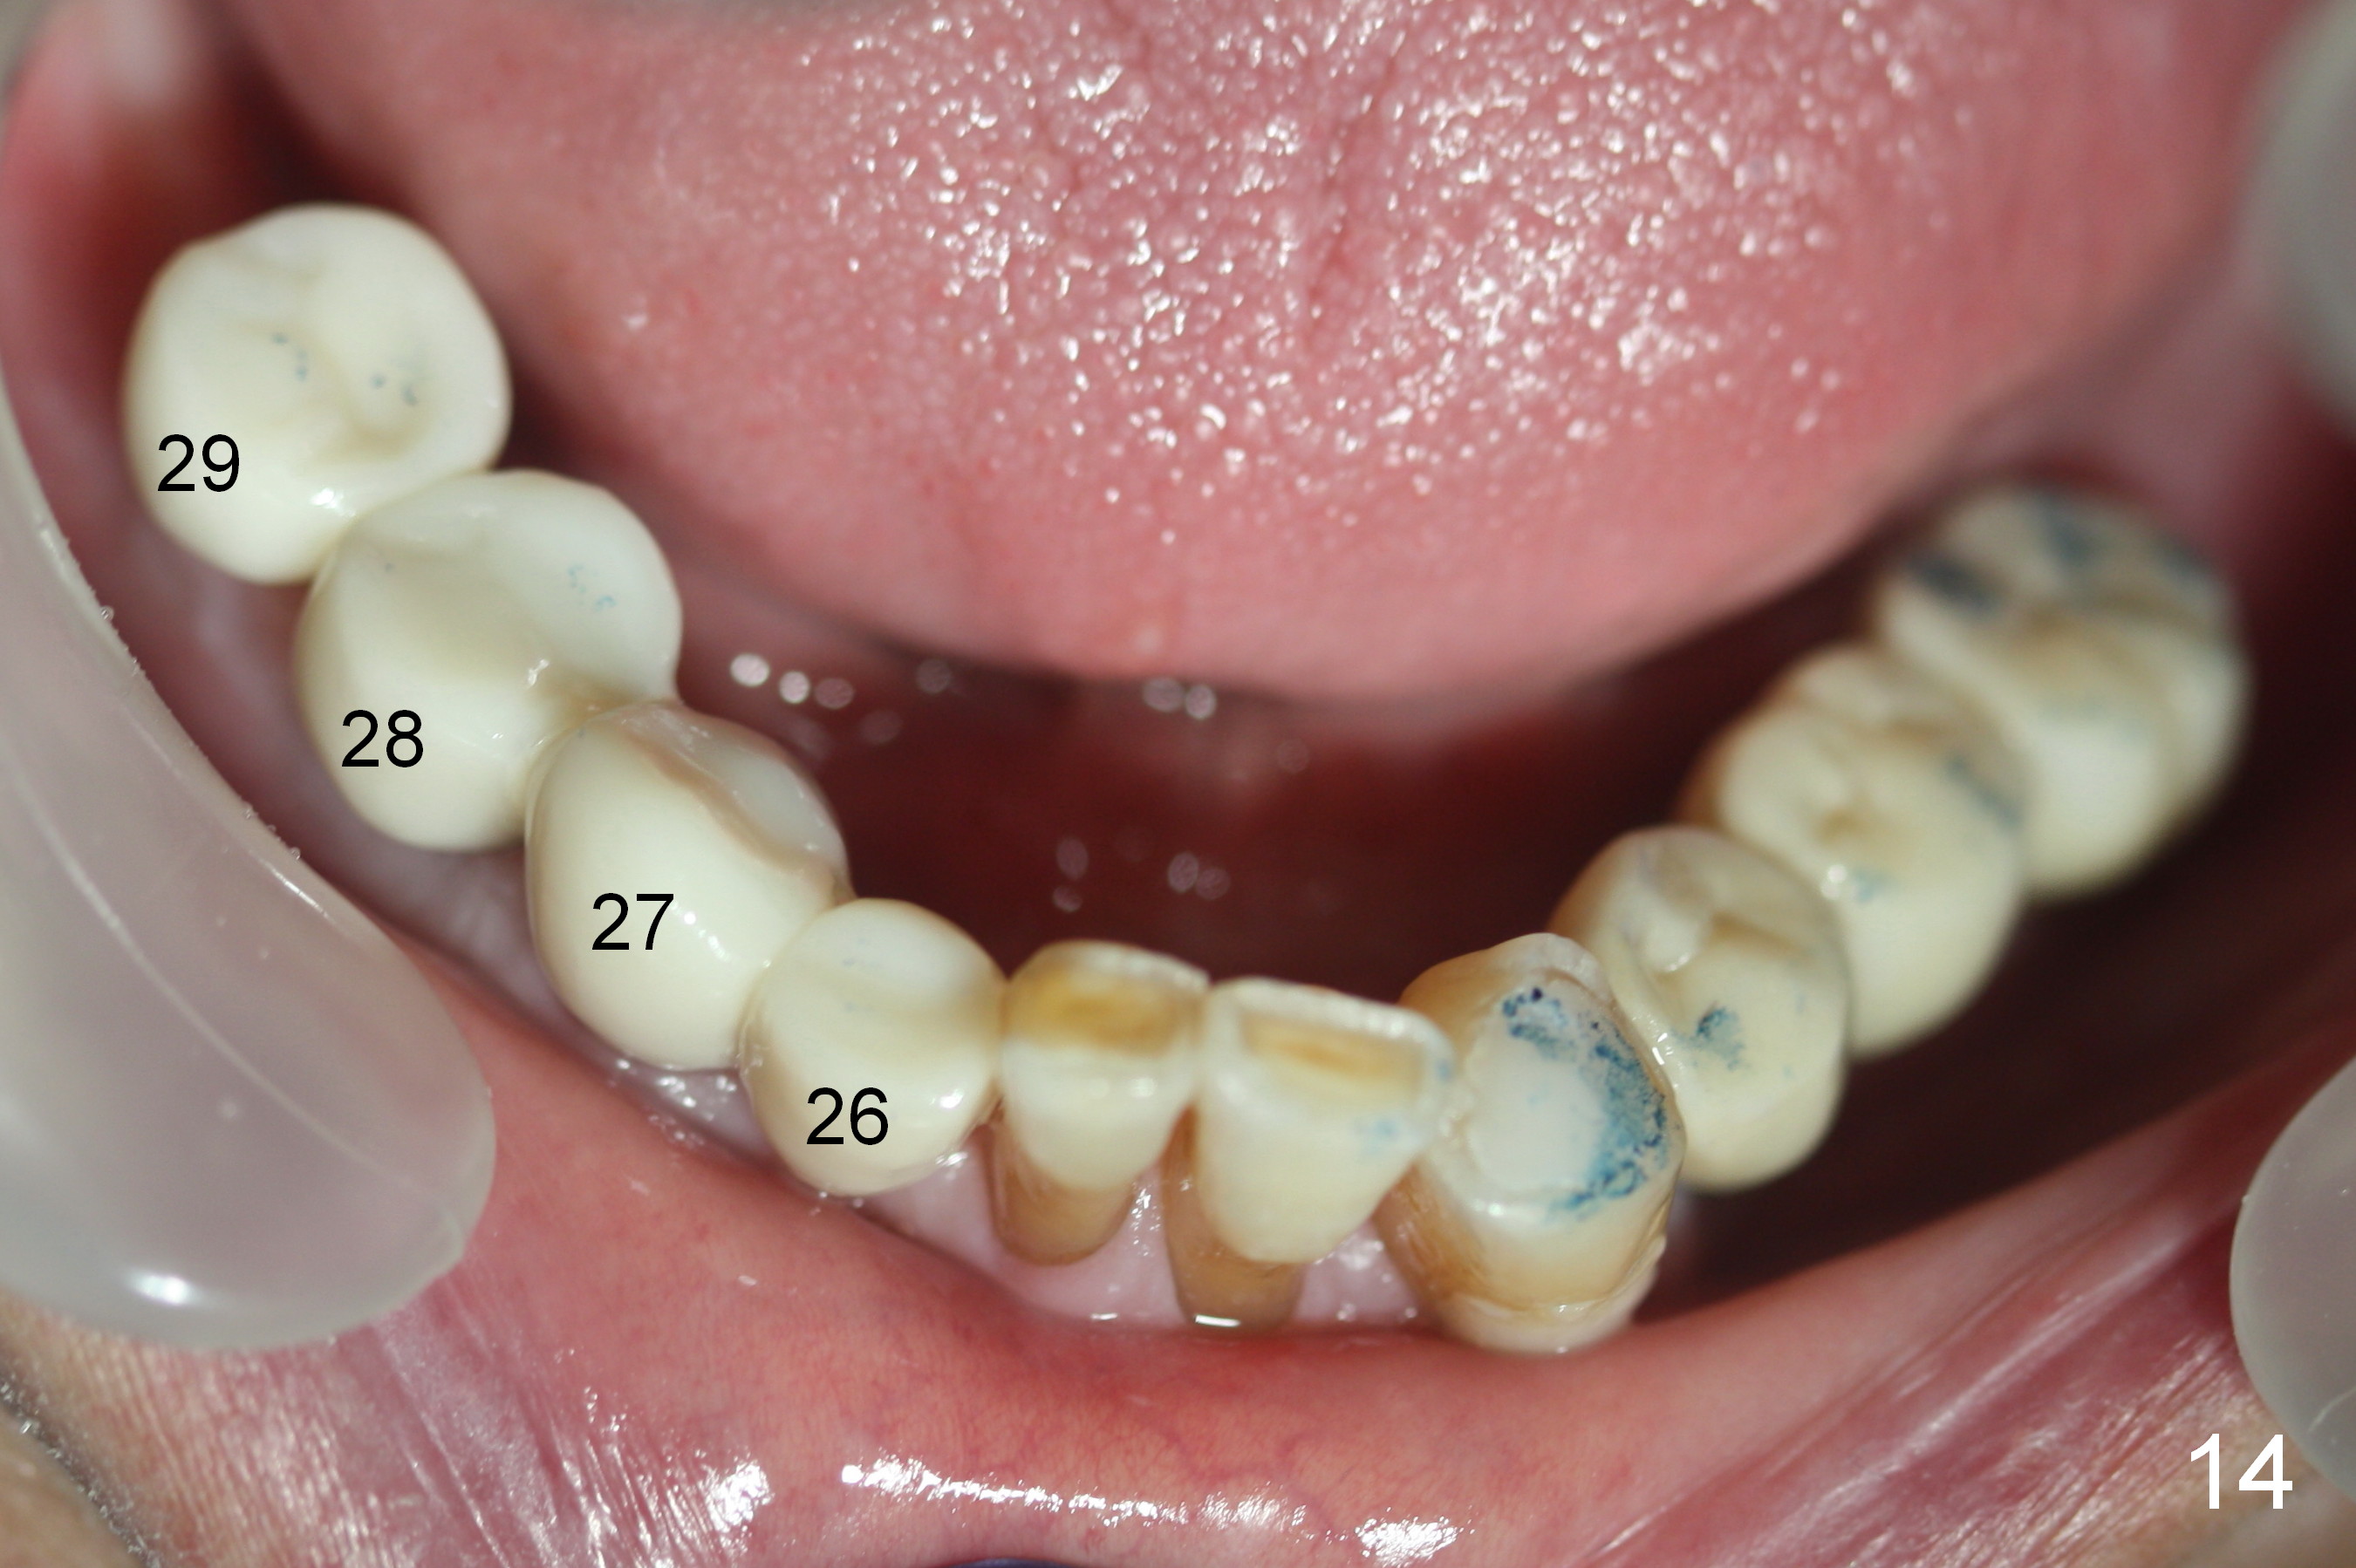

In fact, the crowns are splinted between #26-28, while the one at #29 is single unit (Fig.14). The patient is concerned that the bite on the lower right side is not strong. The occlusion for the most distal crowns should be tight.

14